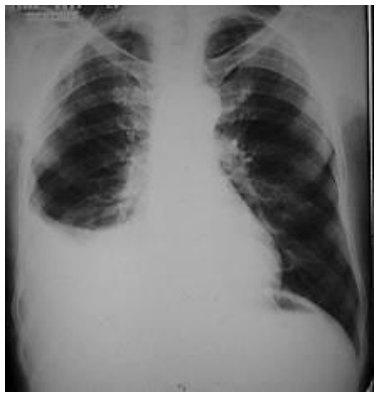

Homem, 48 anos de idade, tabagista de longa data, comparece na Unidade Básica de Saúde (UBS) por estar mais cansado que o habitual em esforços cotidianos. Em radiografia realizada após a primeira consulta, o médico percebe o achado apresentado a seguir:

Enunciado 4806630-1

Em relação ao caso descrito, a melhor conduta é: